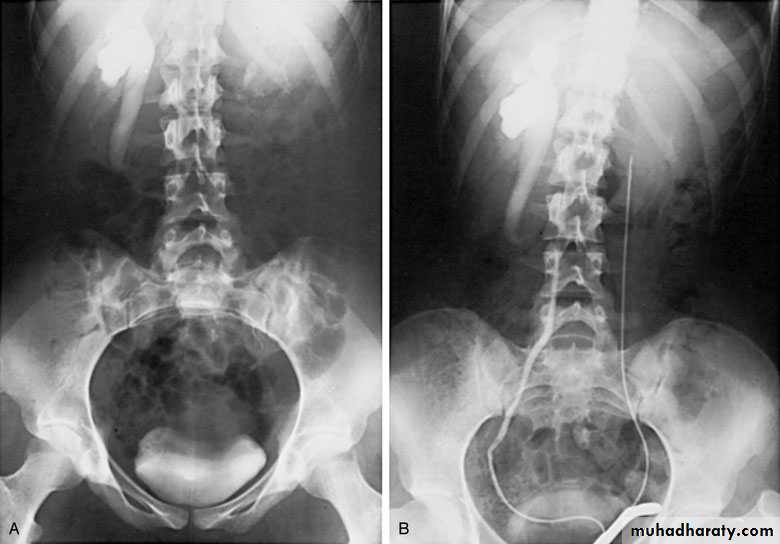

Pyonephrosis

Pyonephrosis refers to infected hydronephrosis where the kidney is converted into a sac containing pus associated with suppurative destruction of the parenchyma of the kidney, in which there is total or nearly total loss of renal function.It is usually unilateral

Causes

Infected hydronephrosis

Following acute pyelonephritis

Complication of renal calculus disease

Investigations

GUE + C&S + blood C&SCBC

KUB

U/S

IVU

CT scan

Treatment

• It is Surgical Emergency that needs drainage

• ..nephrostomy: --percutaneous

• -- open

• .. JJ stint

The stone is removed

nephrectomy